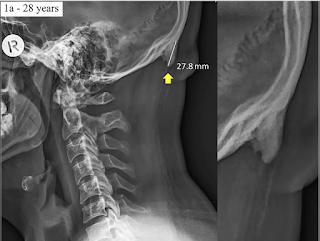

L’articolo medico (Prominent exostosis projecting from the occipital squama more substantial and prevalent in young adult than older age groups, di David Shahar e Mark G. L. Sayers, in Nature Scientific Reports) si limita a notare di aver osservato, in un campione di pazienti australiani, una frequenza maggiore che in passato di formazione di piccole sporgenze ossee e ipotizza che il fenomeno possa essere dovuto alla posizione della testa assunta durante l’uso di dispositivi mobili.